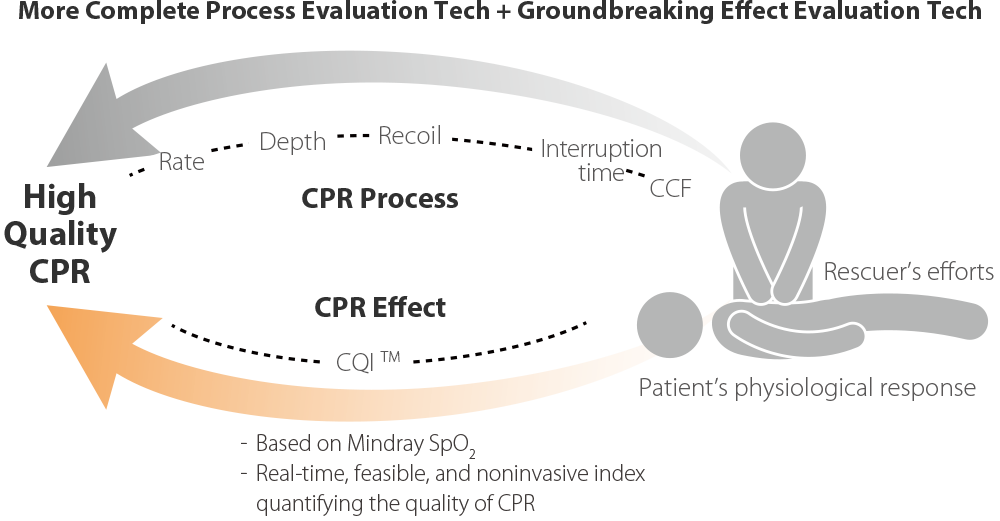

Triangle de sauvetage, plus complet

- Les protocoles de dĂŠbriefing structurĂŠs du D60 amĂŠliorent les performances des ĂŠquipes de rĂŠanimation lors de rĂŠanimations ultĂŠrieures.

RĂŠanimation plus rapide

DĂŠbriefing structurĂŠ

- Les protocoles de dĂŠbriefing structurĂŠs du D60 amĂŠliorent les performances des ĂŠquipes de rĂŠanimation lors de rĂŠanimations ultĂŠrieures.